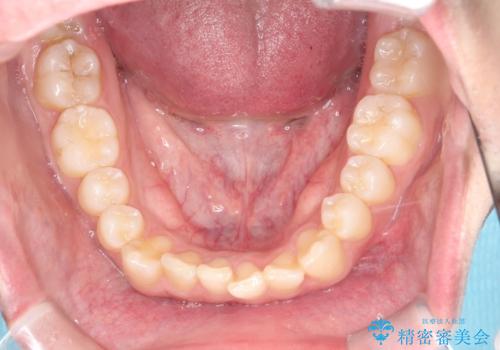

- 八重歯が気になるとのことでご来院されました。お口の中を確認すると、上の前歯がスペース不足で押し出され、少し前に出ている状態でした。抜歯せずに整えるため、奥歯を少しずつ後ろに動かしながら(遠心移動)、歯と歯の間をわずかに削るIPRを行ってスペースを作ることにしました。また、上下の噛み合わせを整えるために2級ゴム(エラスティック)を使用する方針を立てました。

マウスピースを段階的に交換しながら、奥歯を少しずつ後ろへ動かし、八重歯がきれいに並ぶよう調整しました。前歯の突出感を抑えるためにIPRを行い、スムーズに配列。さらに、2級ゴムを活用して噛み合わせも改善しました。治療後は、自然な歯並びになり、笑顔に自信が持てるようになったと喜んでいただきました。